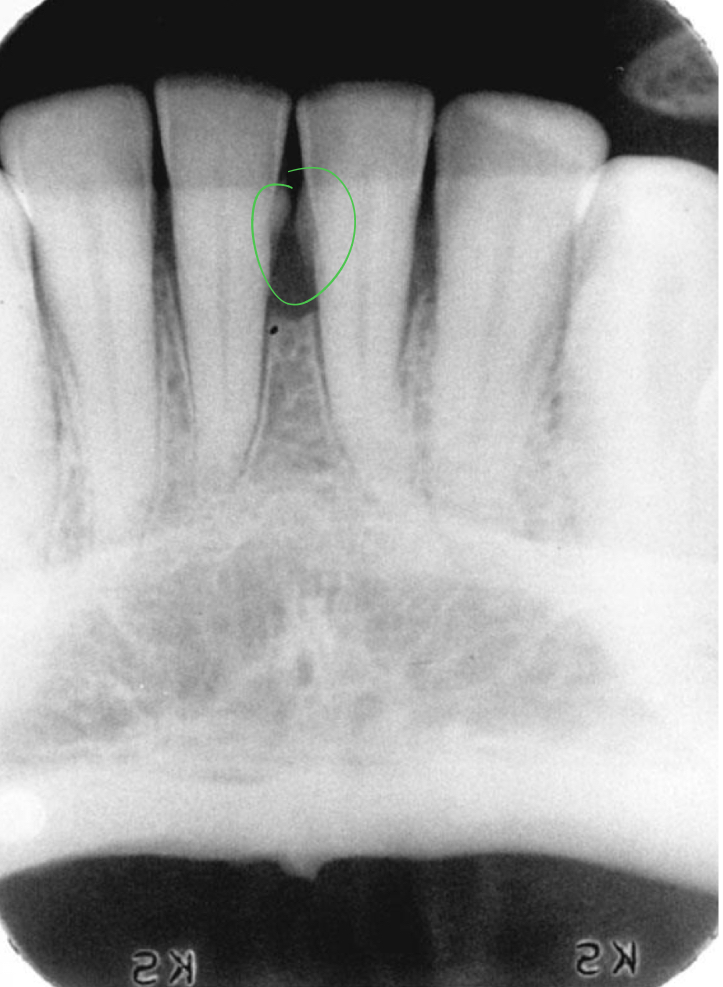

Bone loss

Difference between the physiologic bone level and height of remaining bone

Horizontal vs vertical

Horizontal bone loss

Beyond the 1.5mm-2.00 mm apical to the CEJ

Slight bone loss

1-2mm (crestal changes)

Moderate bone loss

3-4 mm (loss of 10-33%)

Severe bone loss

5mm or more (33% or more)